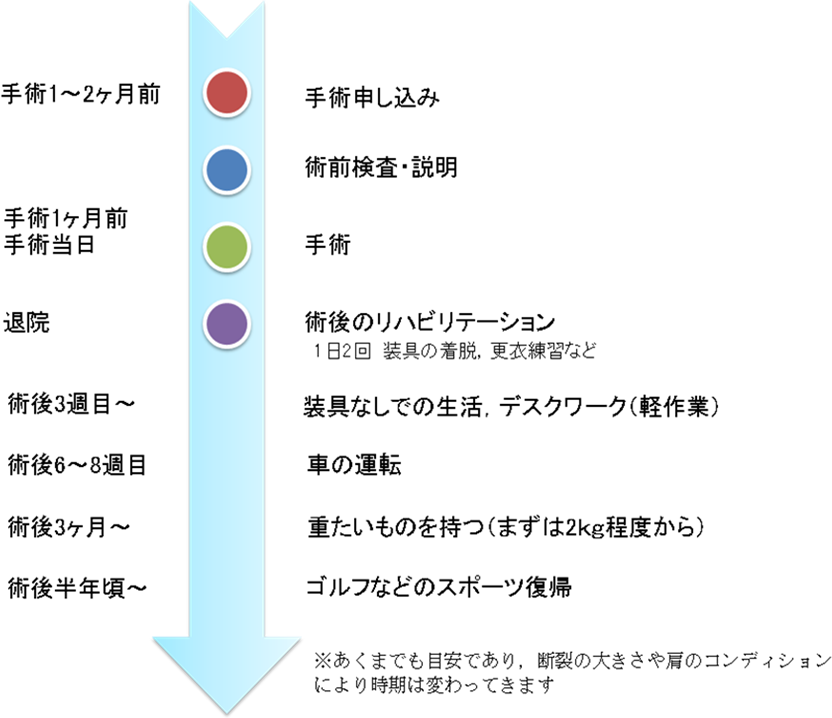

手術前から退院後までの流れは?

術後経過は?

術後約3週間の装具固定期間が過ぎると、徐々に肩関節ならびに肩甲骨の動きの改善を図ります。

術後6~8週で車の運転が可能になり、術後3ヶ月頃から徐々に負荷をかけていきます。

術後半年以降に肩の状態に応じてゴルフなどのスポーツも可能になります。